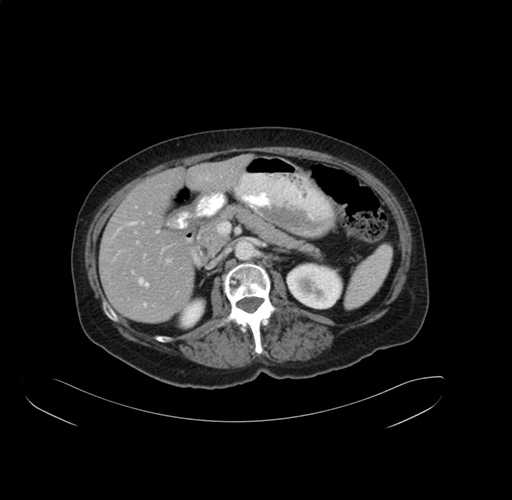

Pre-Chemo: Axial Venous

Axial Venous